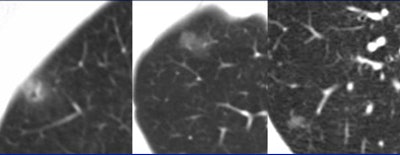

| Three focal ground-glass opacities (GGO) show the variety of presentations at MDCT. The lesion at left has a hazy appearance, with uniform surface lucency. The nodule in the center image is more subtle; no architectural distortion can be seen in the surrounding parenchyma. The GGO at right is rounder and smaller. All images courtesy of Dr. Ella Kazerooni. |